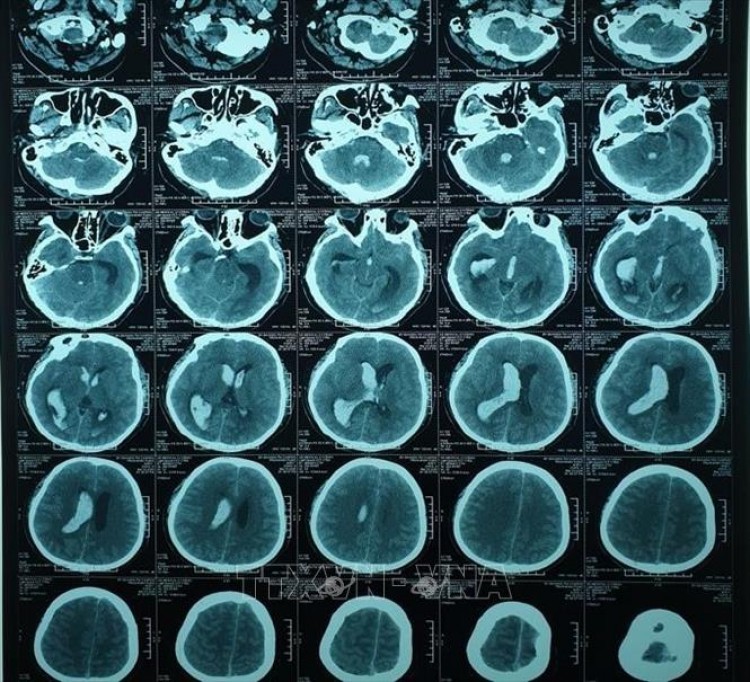

Hình ảnh chụp cắt lớp vi tính não bệnh nhân trước can thiệp. Ảnh: TTXVN phát

Kết quả chụp cắt lớp vi tính sọ não cho thấy bệnh nhân bị chảy máu não, tràn vào hệ thống não thất (những phần hốc, xoang chứa nước bên trong lớp xương sọ), gây dãn toàn bộ hệ thống não thất.

Hội chẩn đánh giá, các bác sỹ nhận định đây là ca bệnh nặng, nguy cơ tử vong gần như hoàn toàn nếu không xử trí kịp thời. Sau khi chụp hình mạch máu não để loại trừ nguyên nhân gây chảy máu, một ống thông dẫn lưu não thất ra ngoài đã được đặt, nhằm làm giảm áp lực nội sọ cho bệnh nhân. Kết quả chụp cắt lớp vi tính cho thấy hệ thống não thất đã bớt giãn nhưng vẫn còn tụ máu nhiều, khả năng tắc ống dẫn lưu là rất cao.